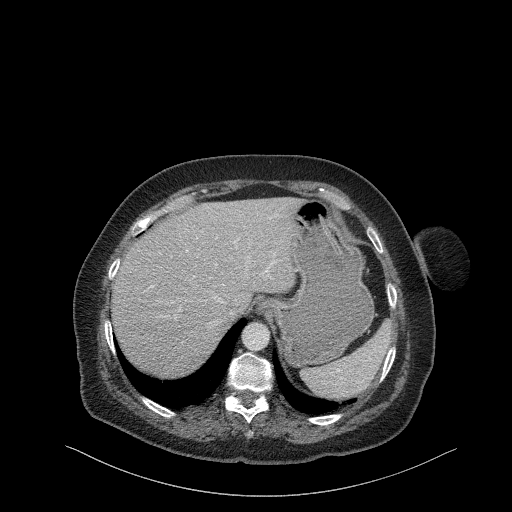

Generated VENOUS CT scan (A→B translation)

No window - Raw intensity values

Lung window (WL -600, WW 1500 β†’ Low βˆ’1350, High +150)

Mediastinum window (WL 40, WW 400 β†’ Low βˆ’160, High +240)